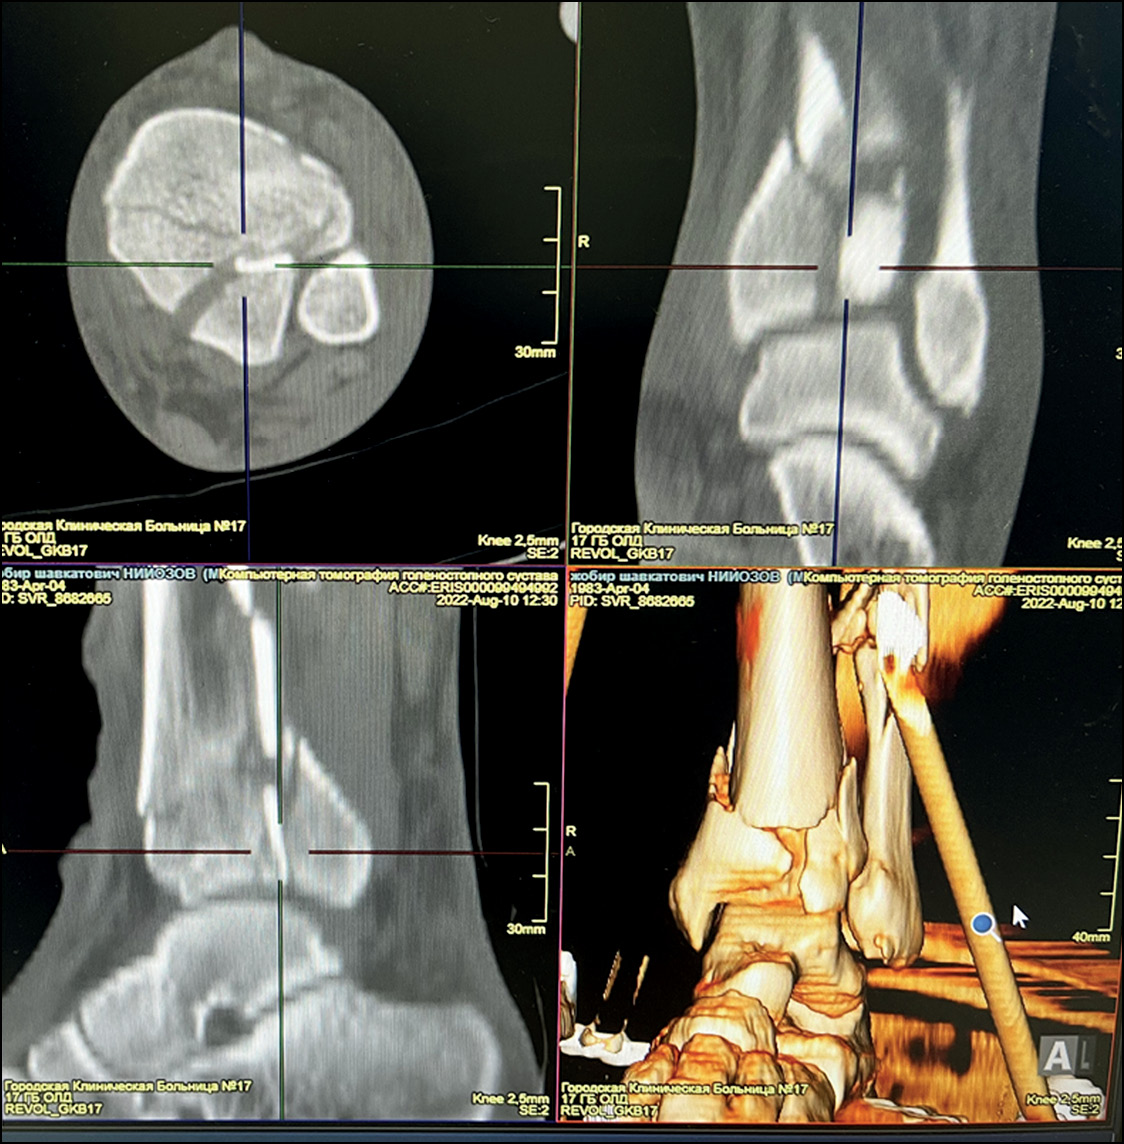

Пациент Н., мужчина, 39 лет. Травма в результате падения с высоты около 3 м. По данным КТ диагностированы внутрисуставные переломы дистального метаэпифиза большеберцовой кости слева со смещением отломков и нижней трети малоберцовой кости со смещением отломков (АО 43–2) (рис. 3). Кожные покровы IC-2. Сопутствующих повреждений нет. Через 5 часов после поступления в приёмное отделение осуществлена фиксация левой большеберцовой кости в аппарате наружной фиксации, выполнено восстановление длины и оси левой голени. Проведена компьютерная томография, на основе которой сформирован файл STL, на 3D-принтере распечатан прототип перелома.

Рис. 3. Пациент Н., 39 лет, состояние костных фрагментов до внутренней фиксации (компьютерная томография).